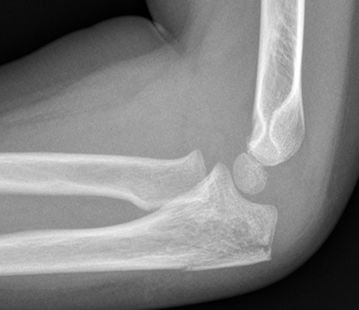

Supracondylar fracture with posterior angulation

Off-ended supracondylar fractures (Gartland Type 3)

- High risk of neurovascular compromise.

- Requires urgent Orthopaedic review and open reduction and internal fixation (ORIF) in the operating theatre.

- If applying a resting slab in ED, plaster arm in current position. Do not flex elbow.

Displaced supracondylar fracture